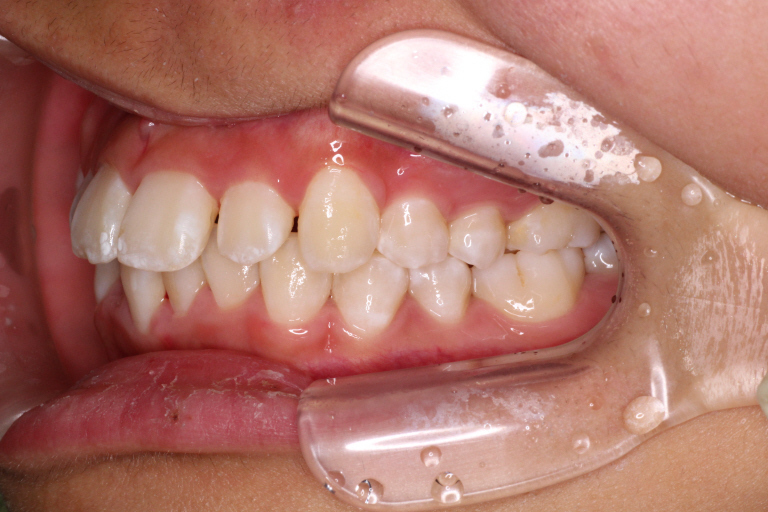

最後のアライナーが終わった時の口腔内写真です。

前歯のがたつきはなくなり、カリエール後にできていた隙間もなくなっています。

奥歯も1歯対2歯の関係で咬めていることがわかります。

通常は歯の並びを微調整するために口腔内を再スキャンし、歯の並びを再設計すること(リファイメント) を2,3回行いますが今回のケースは一回目で満足のいく結果が得られたのでここで保定期間に入りました。